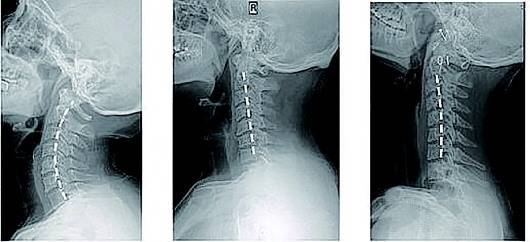

答案:平山病(hirayama disease,hd).